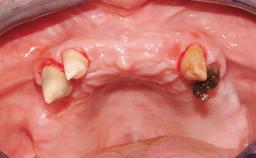

Immediate Loading of Eight Implants in the Maxilla and Six Implants in the Mandible and Final Restoration with Three-Unit and Four-Unit FDPs

Extensive scientific evidence has confirmed that immediately loaded implants with fixed full-arch provisional restorations can osseointegrate with success rates similar to conventionally or delayed loaded implants. A number of immediate-provisionalization techniques for edentulous jaws have been described. Some protocols differ when it comes to prefabricated provisional templates versus complete denture conversion; intrasurgical impressions versus direct relining; and cemented versus screw-retained provisional restorations. In this context, complete-denture conversion has been proposed for either intrasurgical impressions or direct relining. Another possibility is the utilization of a prefabricated provisional to be adapted either in the mouth (by direct relining) or in the laboratory (on a working model obtained from an intrasurgical impression).

Case Type Edentulous Maxilla

Soft Tissue Contour and Volume Slightly compromised